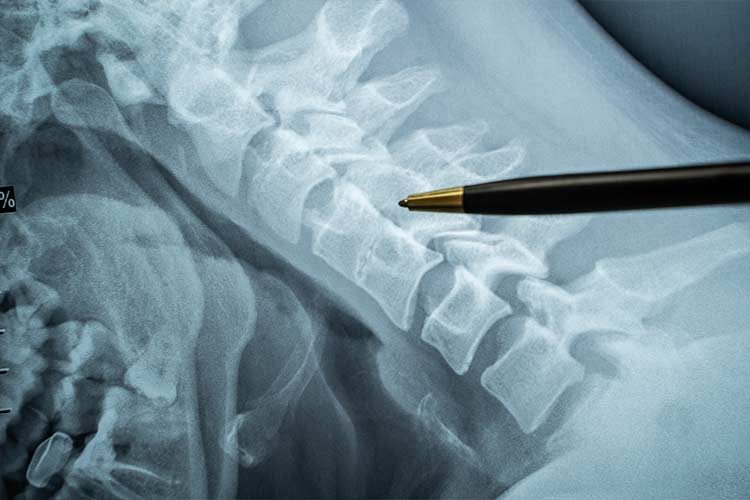

However, when you have pain that persists for three to six months, it’s known as chronic pain. It has the potential to become debilitating and interfere with many aspects of your daily life – both at home and at work. Underlying health conditions like arthritis or fibromyalgia (muscle pain all over) or an injury sustained in a car accident can result in chronic pain. Cancer and cancer treatments may also cause chronic pain, especially in the lower back.

The first step in treating chronic pain is to determine the source, which may or may not be possible to pinpoint. Chronic pain has many causes, including injuries, illnesses, and prolonged physical, emotional, or social stress. When the cause can’t be identified and resolved, the focus turns to managing the pain.